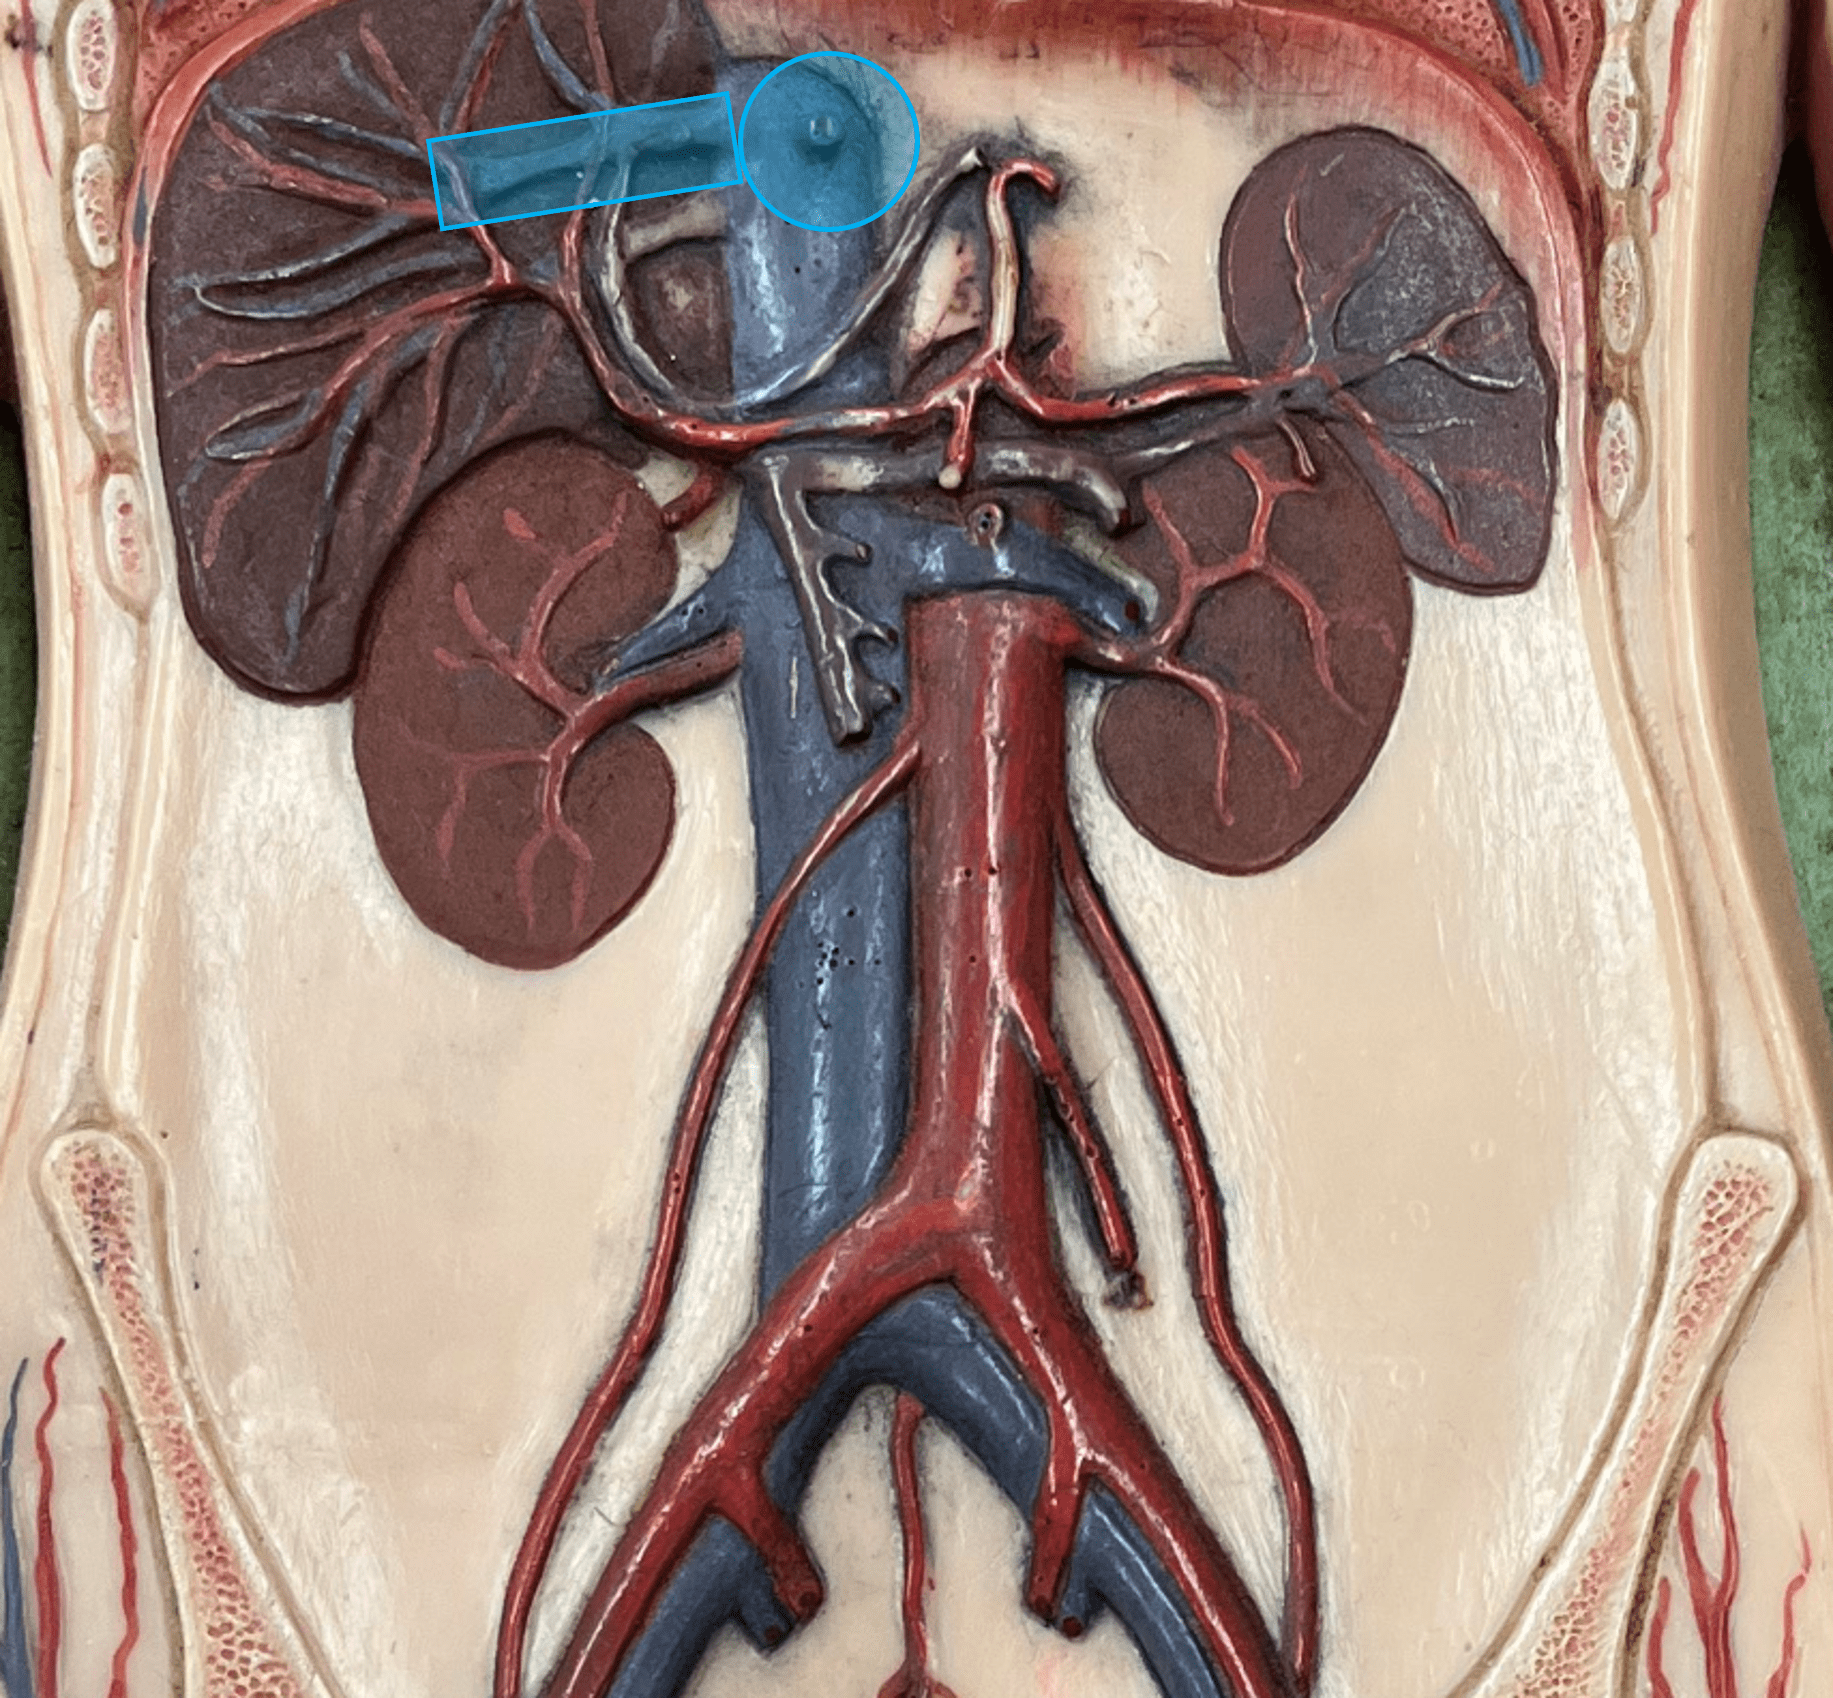

tunica media

renal vein

• A vein of the abdomen.

• Drains the kidneys.

• Empties into the inferior vena cava.

• On the inferior vena cava, inferior to the hepatic veins and superior to the gonadal veins.

• Drains the kidneys.

• Empties into the inferior vena cava.

• On the inferior vena cava, inferior to the hepatic veins and superior to the gonadal veins.